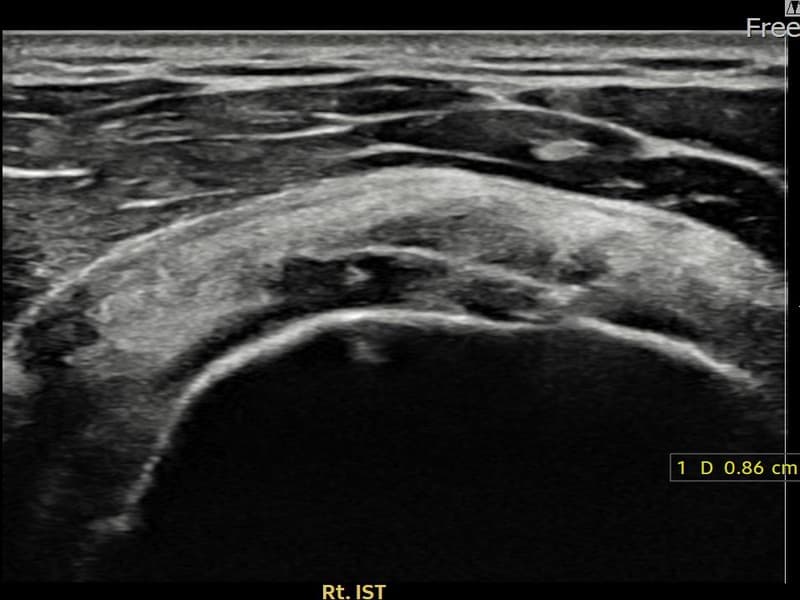

시술 전 초음파 측정 결과 파열 크기는 7mm × 3mm (힘줄 두께의 약 32% 결손)로 확인되었습니다. 시술 전 초음파에서 우측 극하근건 관절면측의 에코 단절과 힘줄 결손 소견이 확인되었습니다. 시술 후 초음파에서 파열 부위에 재생 조직이 형성되고 힘줄 연속성이 회복된 것이 관찰되었습니다.

30대 후반 남성 환자분으로, 우측 어깨 후방 통증이 수개월째 지속되어 내원하셨습니다. 팔을 뒤로 젖히거나 외회전할 때 심한 통증이 있어 운동이나 스포츠 활동에 큰 제약이 있으셨습니다. 초음파 검사에서 우측 극하근건 관절면측 부분파열이 확인되었으며, 초음파 유도 하 축소봉합술을 시행하였습니다. 시술 후 보조기 착용과 단계적 재활 운동을 통해 회복을 진행하였고, 시술 11주 후 추적 초음파에서 힘줄 연속성이 회복되고 외회전 기능이 정상화된 것이 확인되어 스포츠 활동에 복귀하셨습니다.